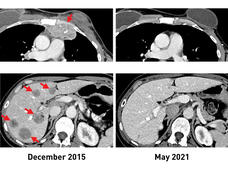

TIL therapy scan

NCI Study Advances Personalized Immunotherapy for Metastatic Breast Cancer

NCI researchers have shown that an experimental form of immunotherapy that uses a person's own tumor-fighting immune cells could be used to treat people with metastatic breast cancer who have exhausted all other treatment options.